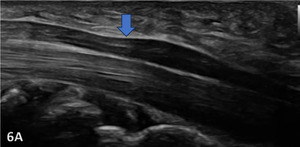

The median nerve is clearly identifiable in SAX by a well circumscribed ovoid structure with hypoechoic fascicles in a honeycomb-like pattern deep to the roof of the carpal tunnel, the flexor retinaculum, and more superficial to the flexor digitorum superficialis and flexor digitorum profundus tendons. The median nerve is also very compressible and will alter its shape depending on the volume of the anatomical spaces with which it courses. The median nerve cross-sectional area (CSA) can be measured in four sites: 1) the proximal border of the pronator quadratus muscle, 2) proximal to the carpal tunnel inlet, 3) at the tunnel inlet, and 4) at the tunnel outlet.9

Normal Sonographic Appearance